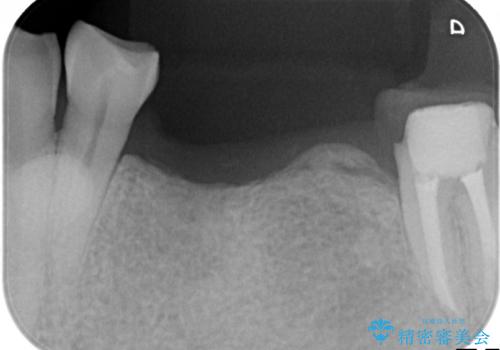

- 左下奥歯が虫歯で抜歯になってしまったため、インプラントにしたいといらっしゃった方の症例です。

欠損部位である左下5、6番目にインプラントを埋入し、オールセラミッククラウンによる補綴を行いました。

左下7番目は再根管治療を行い、オールセラミッククラウンによる補綴を行いました。